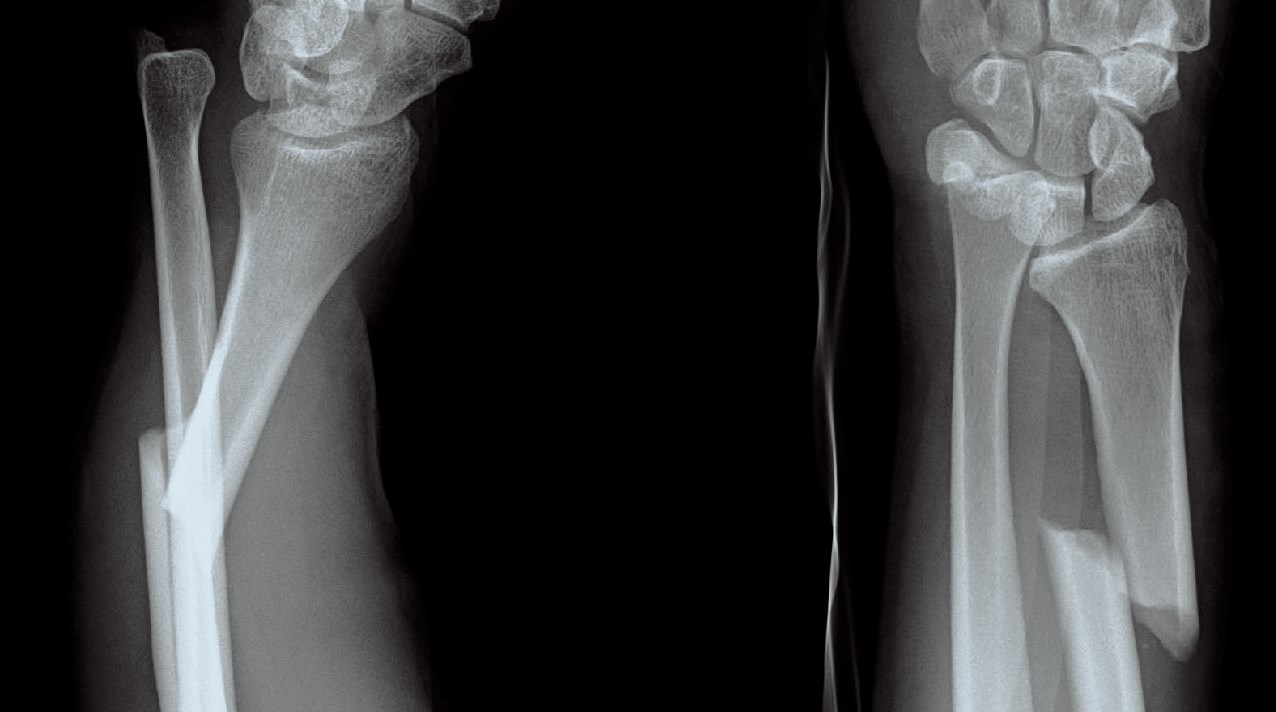

Bennetfraktur

Bennetfraktur är en intraartikulär luxationsfraktur genom basen av metacarpale I. Metacarpalbasen tenderar att luxera genom APL senans dragning i radiell-proxmal riktning. Frakturen behöver därför i princip alltid reponeras och immobiliseras internt med stift. Kan se väldig beskedlig ut på primära bilder men dislocerar succesivt genom senans dragning – klassificeras därför som ”lurig”.

Mekanism vid Bennetfraktur

Bennetfraktur där det ulnara fragmentet i basen på metkarpalen hålls kvar med hjälp av ligament i karpus. På grund av drag i abductor pollicis longus (APL) uppstår nästan alltid en diastas i frakturen. Diastasen i ledytan ger sekundärt artros. Dessa frakturer kräver således exakt fixation – vanligen i form av stift eller skruv.